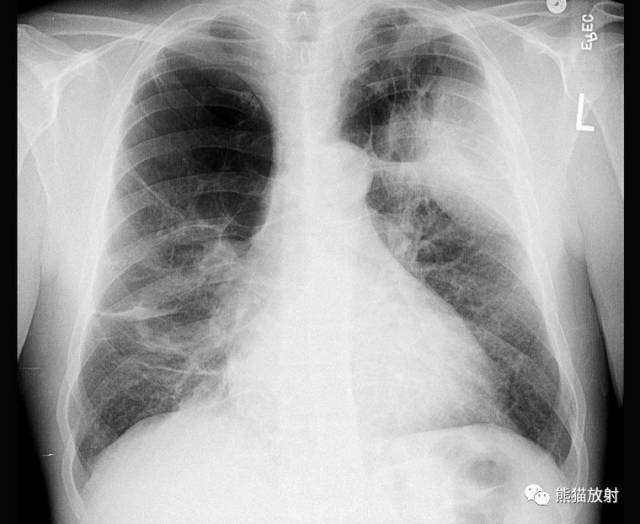

| 双肺弥漫性肺气肿 |

大多将肺部的过度充气膨胀以及肺血管纹理变细和减少现象作为诊断肺气肿的两个主要X线表现。但肺血管纹理的改变实际上具有如下两种类型:

(1)肺纹理减少型:这种肺气肿的三项主要X线表现为:①肺过度充气膨胀;②肺血管纹理减少;③肺大泡。肺过度充气膨胀,表现为肺透亮度加深和肺容积增大。肺容积增大表现横膈位置下降和膈顶变平、胸骨后肺透亮区增宽、胸廓呈桶状及心影呈垂直型。这种类型常多见于全小叶型肺气肿。

(2)肺纹理增多型:其X线表现肺纹理不是纤细减少,反而比正常者更为显著。有的轮廓不规则、不清晰,提示有严重的慢性支气管炎现象。肺部只有轻度或中度的过度肺充气膨胀(肺大泡很少见到)。这种类型多见于小叶中央型肺气肿。